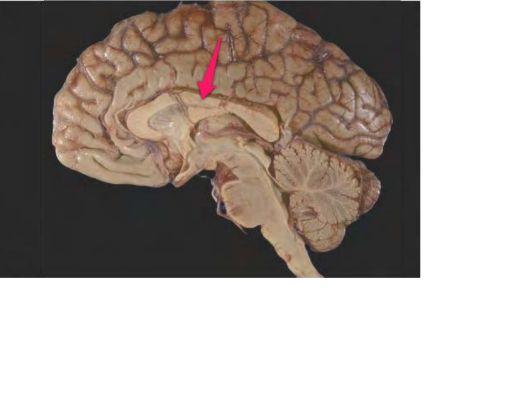

corpus callosum